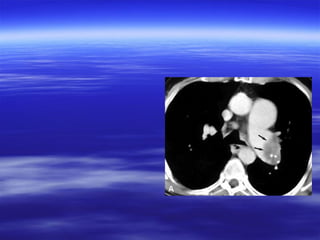

CT findings ooff aaccuuttee ppuullmmoonnaarryy

eemmbboolliissmm

VVaassccuullaarr aabbnnoorrmmaalliittiieess::

 IInnttrraalluummiinnaall ffiilllliinngg ddeeffeeccttss tthhaatt ffoorrmmss aann aaccuuttee

aannggllee wwiitthh tthhee vveesssseell wwaallll && mmaayy bbee ssuurrrroouunnddeedd

bbyy ccoonnttrraasstt mmaatteerriiaall ((ppoolloo mmiinntt ssiiggnn oorr rraaiillwwaayy

ssiiggnn((..

 TToottaall ccuuttooffff ooff vvaassccuullaarr eennhhaanncceemmeenntt..

 EEnnllaarrggeemmeenntt ooff tthhee oocccclluuddeedd vveesssseell..

CT findings ooffaaccuuttee ppuullmmoonnaarryy eemmbboolliissmm VVaassccuullaarr aabbnnoorrmmaalliittiieess::  IInnttrraalluummiinnaall ffiilllliinngg ddeeffeeccttss tthhaatt ffoorrmmss aann aaccuuttee aannggllee wwiitthh tthhee vveesssseell wwaallll && mmaayy bbee ssuurrrroouunnddeedd bbyy ccoonnttrraasstt mmaatteerriiaall ((ppoolloo mmiinntt ssiiggnn oorr rraaiillwwaayy ssiiggnn((..  TToottaall ccuuttooffff ooff vvaassccuullaarr eennhhaanncceemmeenntt..  EEnnllaarrggeemmeenntt ooff tthhee oocccclluuddeedd vveesssseell.. AAnncciillllaarryy ffiinnddiinnggss::  PPlleeuurraall bbaasseedd wweeddggee sshhaappeedd aarreeaass ooff iinnccrreeaasseedd aatttteennuuaattiioonn wwiitthh nnoo ccoonnttrraasstt eennhhaanncceemmeenntt..  LLiinneeaarr aatteelleeccttaassiiss..